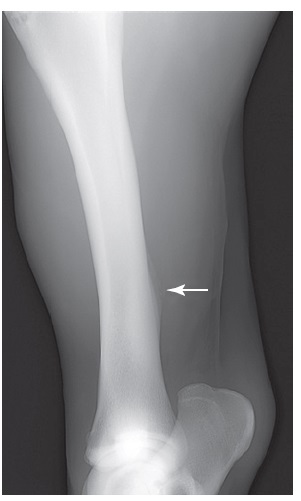

Figure 100-2. A craniolateral-caudomedial oblique radiographic view of a tibia with a midtibial stress fracture. The stress fracture can actually be seen in this horse (arrow), which is unusual because callus normally obscures the fracture.